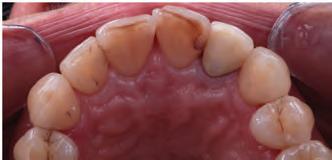

A 31-year-old woman presented with cosmetic concerns regarding her smile and requested a conservative enhancement. After clinical and radiographic analysis, digital 35mm photographs were taken and reviewed by the restorative clinician, technician, and surgeon (Fig 1). A digital impression was taken of the maxillary and mandibular arches using an intraoral scanner (Trios 3, 3Shape; Fig 2), and a smile design was developed with NemoSmile Design 3D software (Nemotec; Fig 3a). This allows for a facially driven smile frame to be created using reference lines of facial and smile proportions and natural teeth shapes and textures from the digital library (Fig 3b).

After developing the simulated mock-up, a 3D-printed resin model was created using CAD software (Fig 4a), and a clear PVS matrix (Exaclear, GC America) was fabricated to replicate the printed diagnostic wax-up using a nonperforated tray (Fig

Fig 1 Preoperative clinical views of a 31-year-old woman presenting with diastemas and limited tooth visibility. (top) Portrait. (center row) Intraoral views. (bottom row) Smile.

4b). This matrix was used to create an intraoral motivational mock-up with bis-acryl composite (Luxatemp Ultra, DMG). This additive mock-up provides the interdisciplinary team with an intraoral translation for evaluation (Fig 5). Upon evaluation of the digital smile frame and the clinical translation, it was determined that multiple esthetic and restorative requirements were necessary for an optimal biologic framework, and the interdisciplinary team determined the best sequence for these procedures. The patient was presented with the interdisciplinary treatment possibilities that included restoring the maxillary anterior teeth and premolars with a minimally

invasive preparationless procedure or with less conservative veneer preparations. The restorative materials discussed included injectable resin composites and ceramic (ie, feldspathic, pressable, machinable). For an optimal biologic framework and health, it was determined that connective tissue grafting would be necessary for treatment of the recessiontype defects on the maxillary left central and lateral incisors, canine, and premolars. The patient opted for the conservative preparationless composite veneers using the injectable resin technique followed by a connective tissue surgical procedure using the tunneling technique.

Fig 2 Digital scan of the preoperative maxillary arch.